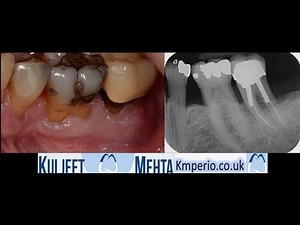

Infection - 1st Molar

Extraction - Broken Tooth